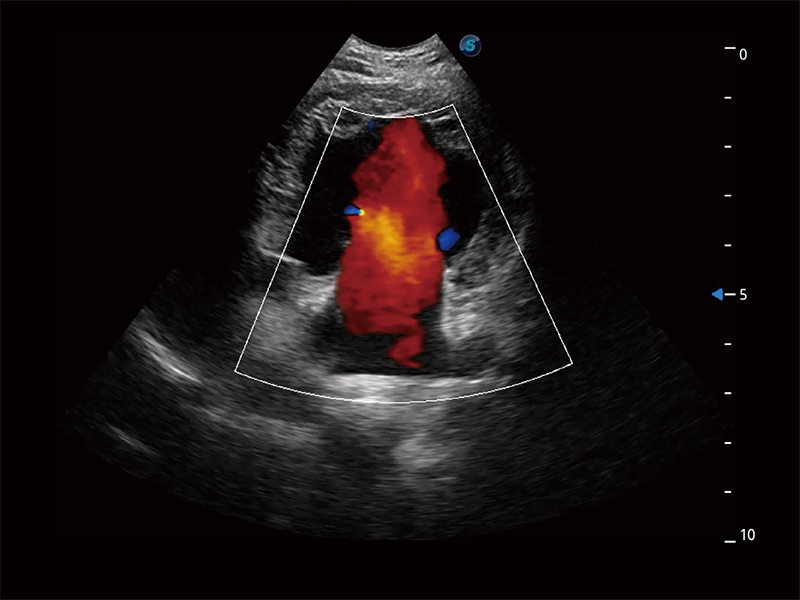

(犬)二腔心血流

得心应手 心脏解决方案

ProPet 80 配备了丰富的心脏探头群、先进的成像技术和专业的心脏测量工具,可帮助动物医生为不同体型和生理结构的动物提供心脏和心肌功能的全面评估。